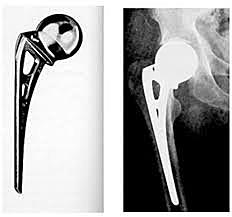

• Fred Thompson

Fred Thompson

consistió en el diseño de endoprótesis metálicas con vástagos medulares para la fijación esquelética. Los vástagos más largos permitían la transmisión de las fuerzas de soporte de peso a lo largo del eje del fémur

• G.K. McKee

G.K. McKee

viajó de Inglaterra a Estados Unidos y se entusiasmó al ver el diseño de la prótesis de Thompson. Regresó a su país y desarrollo un diseño de cotilo sin cementar con superficie articular metálica adaptado al sistema del vástago de Thompson. Las primeras prótesis de McKee estaban hechas de acero.

• McKee-Farrar

McKee-Farrar

investigó también en el vástago de la prótesis y lanzó al mercado un diseño de cuello más delgado. La idea se desarrolló con J. Farrar. En la actualidad el sistema se conoce como prótesis de McKee-Farrar